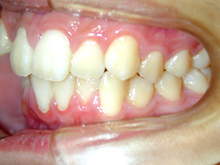

常滑市小林町在住 S.T様(15歳女性)

S.T様は下顎前歯の叢生が主訴でお母様と無料矯正相談で来院されました。

口を閉じる際に口元の緊張があり、横顔に突出感がありました。

以前に上顎前歯の部分矯正をされたご経験があるとお話しされておりました。

そのためか上顎犬歯の横幅(幅径)が通常より少なく思いました。

試料採取より診断の結果、上顎の前歯にも軽度の叢生があり、口元の緊張を改善し、

前歯の叢生の治療のために抜歯が必要であることを説明し、了承が得られたので本格矯正で治療をすすめることとなりました。

上顎前歯に軽度の叢生、下顎前歯に叢生がみられます前歯の上下の接触状態が緊密でなく軽度の舌癖の存在を疑います。

臼歯部は1歯 対 2歯で咬んでいます。

![]() |